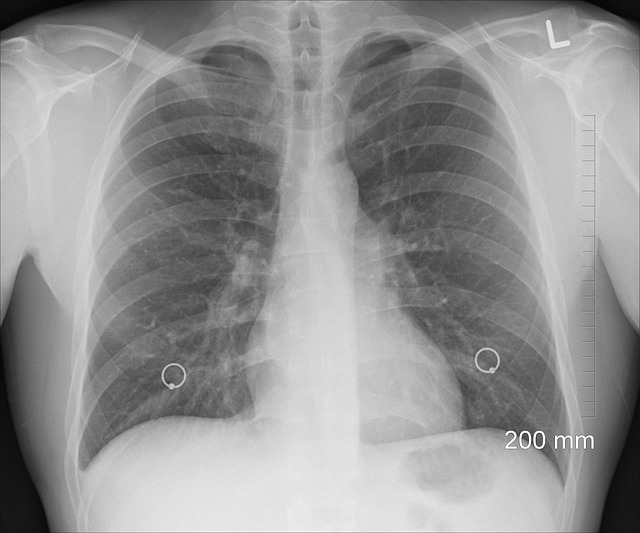

- 흉부 엑스레이: 결핵 진단의 첫 단계로 흔히 사용되는 방법입니다. 폐의 구조를 확인하여 결핵의 징후를 찾습니다. 엑스레이에서 이상이 발견되면 추가 검사를 진행하게 됩니다. 📸